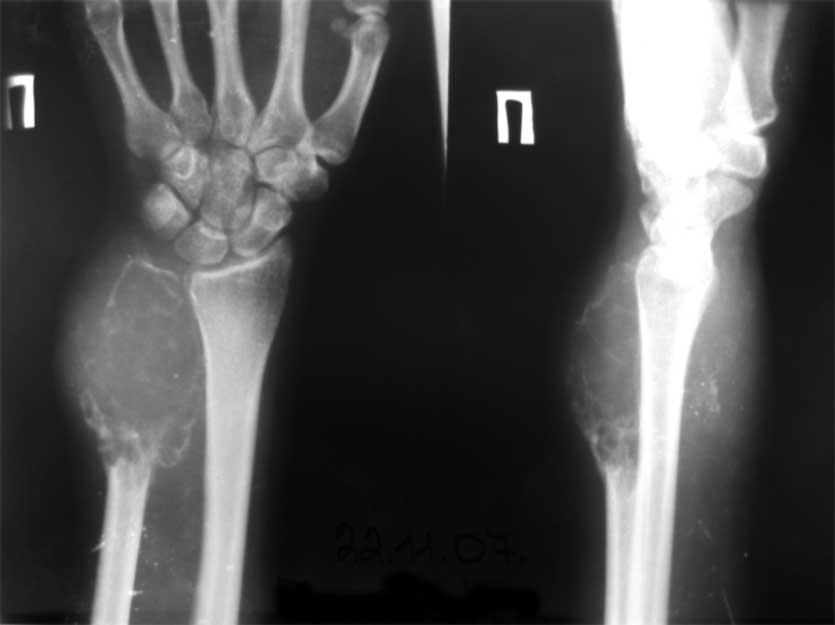

остеобластеокластома локтевой кости

Обратилась пациентка 21 года с опухолью в области н/3 диафиза локтевой кости.

Первые жалобы появились около года назад. Снимков старых под рукой сейчас нет, но опухоль быстро прогрессировала, за полгода увеличилась в размерах более чем в 2 раза. Выполнено несколько гистологических исследований - стеобластеокластома без признаков озлокачествления. После заключительной биопсии на локтевой поврехности предплечья есть рана 5/7 см,не заживет на протяжении 2 мес (натяжение кожи над опухолью), гранулирует, небольшое количество налетов. Планируется резекция, продленная фиксация в гипсе/аппарате - 3-4 мес для формирования контрактуры, уменьшения риска локтевой девиации кисти.

Наличие периостального козырька у основания свидетельствует об вторичном озлокачествлении гигантоклеточной опухоли. Отделяемое неоднократно исследуют цитологически на наличие опухолевых клеток, а также с посевом на микрофлору и чувствительность к а/биотикам. Абластичная резекция в пределах здоровых тканей с замещением дефекта цементном спейсером с антибиотиками в условиях инфекции является адекватным способом лечения.

Привет, Максим! рентгенологически явные признаки малигнизации ГКО.

Уважаемые коллеги, госпитализировали, наконец, эту пациентку, чему не очень рады, как клиническая, так и рентгенологическая картины изменились, кроме того Hb 76.Направил на повторную консультацию к онкологу. Остеобластеокластома может себя так вести?

Клинико-рентгенологически очень похоже на хондросаркому..... Хотя, конечно же, необходимо гистологическое заключение...

Плоховато она выглядит на снимках.

Уважаемые коллеги. По данным рентгенограммы опухоль больше похожа на злокачественную фиброзную гистиоцитому или телеангиоэктотический вариант остеогенной саркомы с поражением кожных покровов. По данным 6 отделения ЦИТО (Бурдыгин В.Н., А.В. Балберкин) и докторской диссертации А.Н. Махсона при поражении низкодифференцированной, т.е. высокозлокачественной опухолью кожных покровов или магистральных сосудисто-нервных структур органосохраняющие оперативные методы лечения не показаны, т.к. имеются отдаленные не диагностируемые метастазы. Показано комбинированное оперативное лечение по принципам неоадъювантной ПХТ.

Может при озлокачествлении (литическая форма), но уж больно похоже на хондро SA.